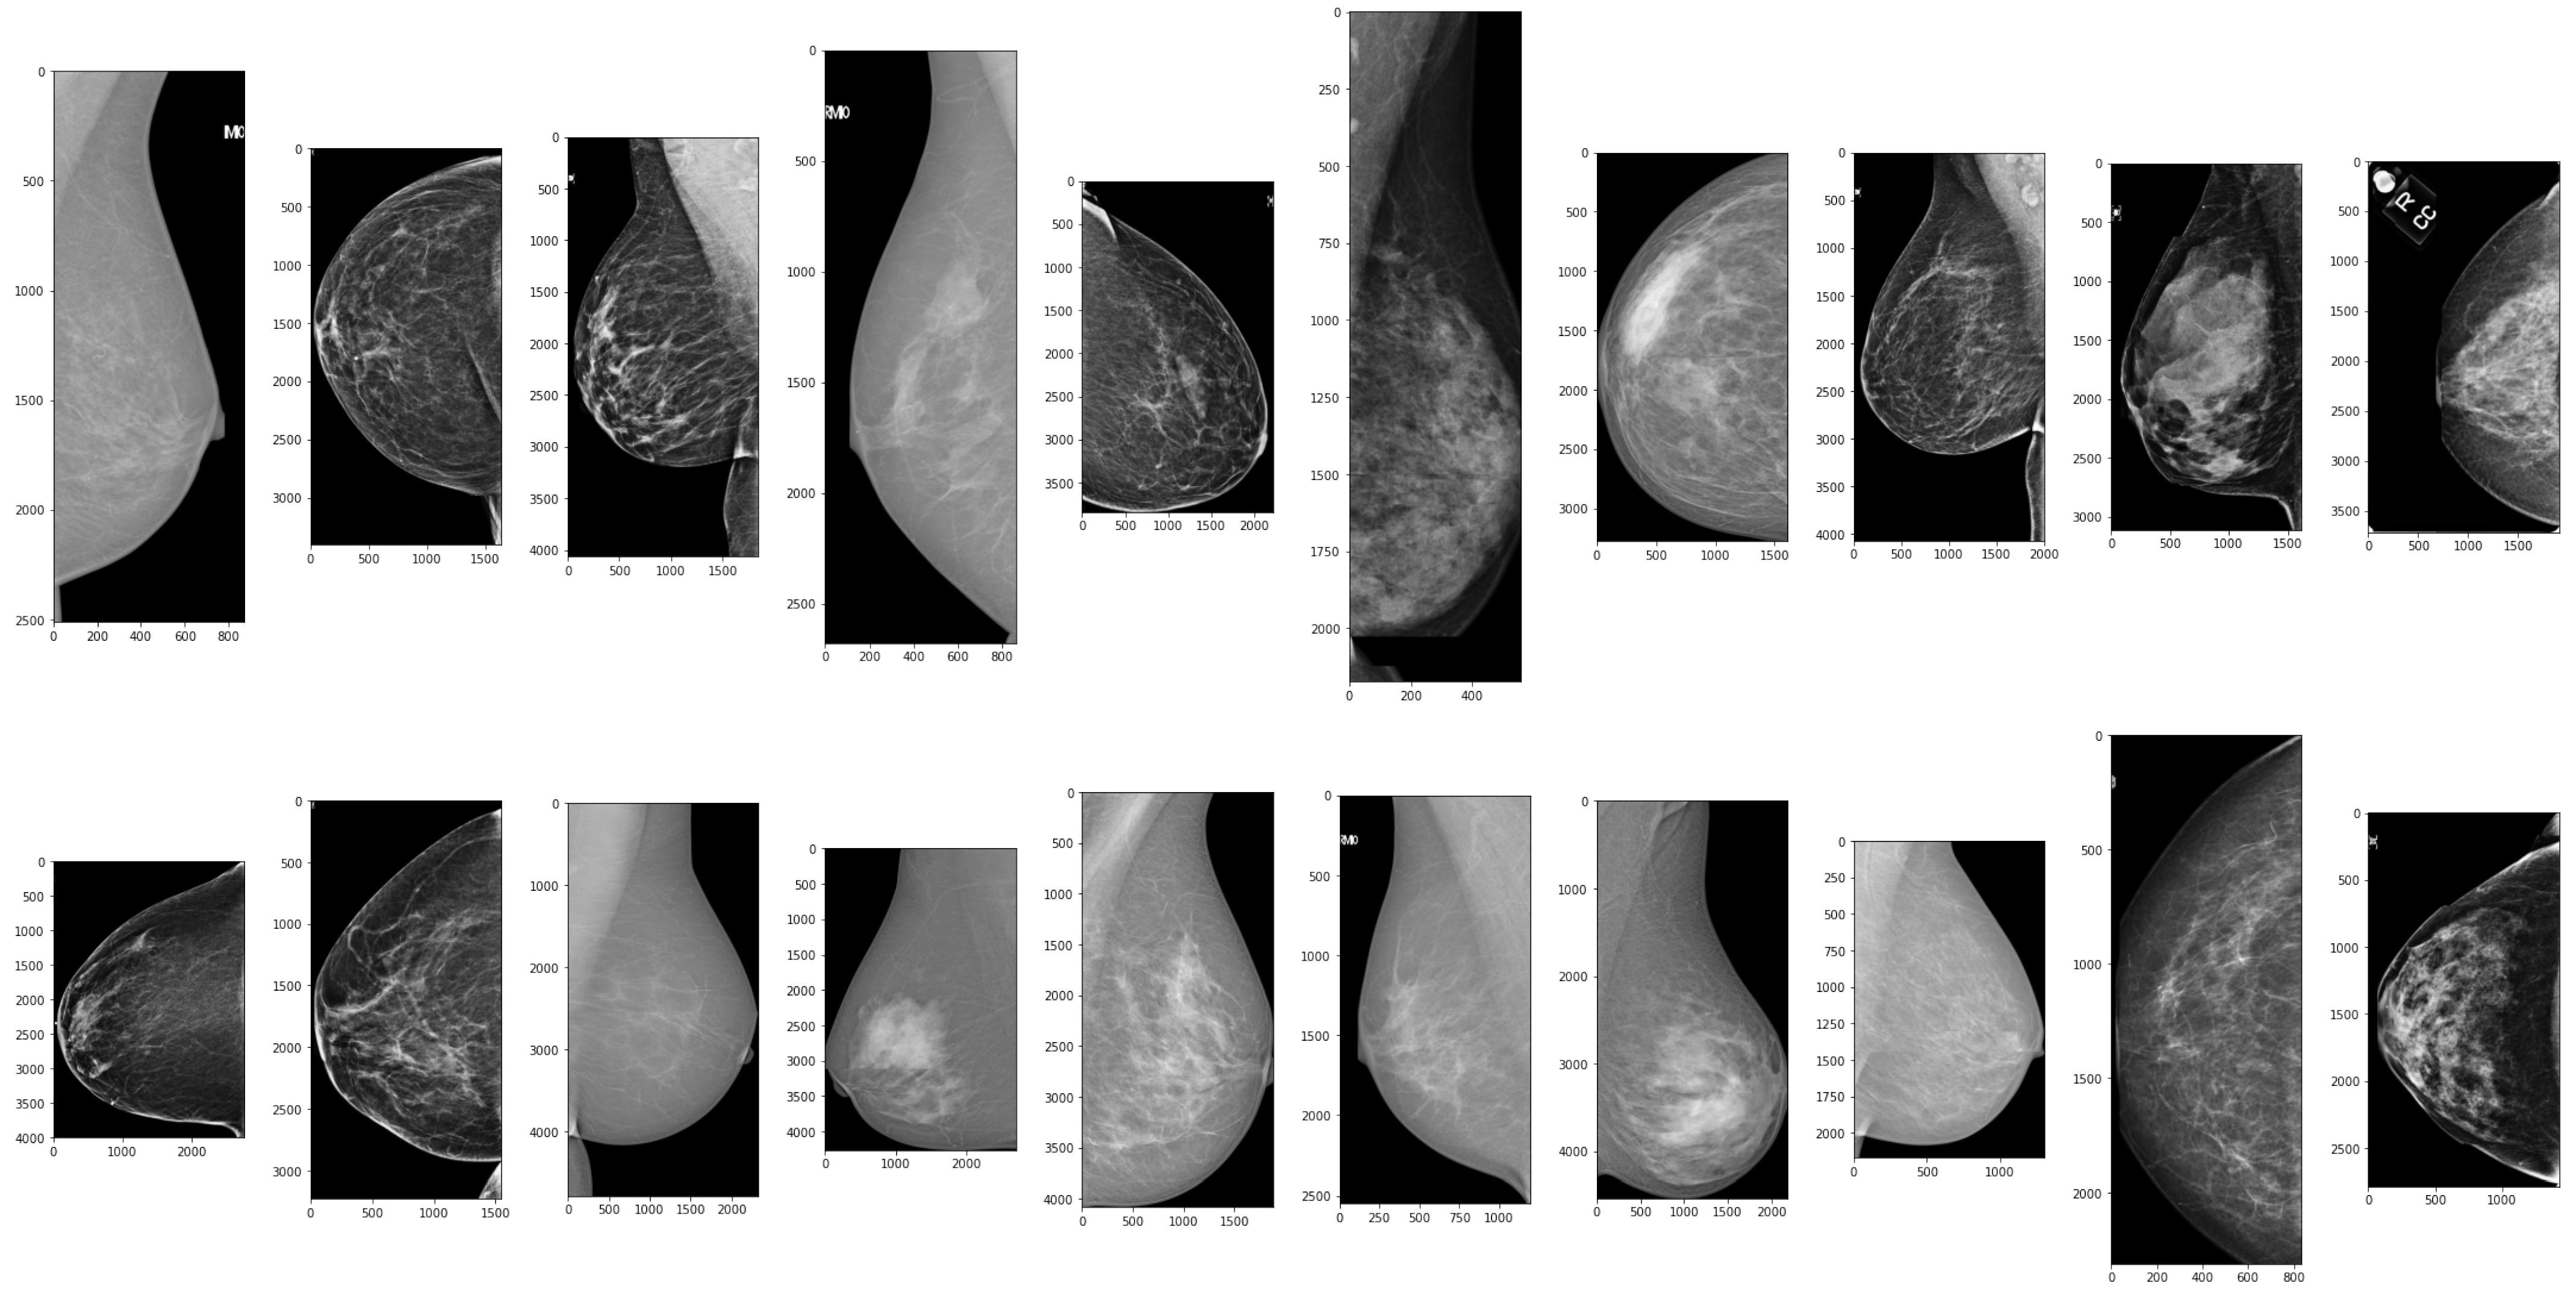

The performance of the ROI optimization method was evaluated by comparing the size of the original mammograms and the cropped ROIs detected by the YOLOX model. Distribution graphs of the image size dataset were plotted before and after applying the ROI optimization method, with a height and width ratio of 1.018, as depicted in Figure 4. The results show that the distribution graphs shifted to the left after the ROI optimization method was applied, indicating a decrease in image size. The mean image size of data decreased by 76.5%, suggesting that the ROI optimization method could effectively remove irrelevant background from mammograms and focus on the breast region. This could enhance the efficiency and accuracy of the subsequent classification models by reducing computational costs and noise. Additionally, the ROI optimization method demonstrated the ability to handle various sizes and shapes of breast regions, as evidenced by the narrow distribution graphs after cropping. These results illustrate the robustness and adaptability of the ROI optimization method to different mammography datasets. Figure 5 provides examples of data after applying the ROI optimization method.

Figure 5.

Examples of data after applying ROI optimization method.